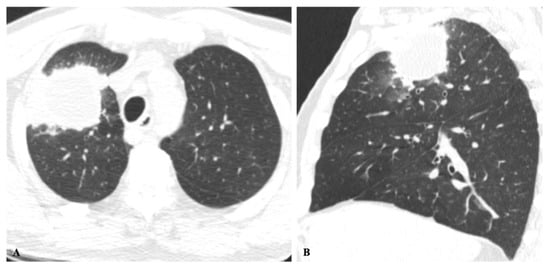

2.2. Non-Resolving Pneumonia

2.3. Chronic Cavitating Disease